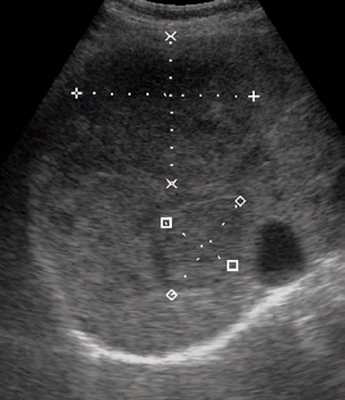

Ультразвуковая картина гемангиомы определяется ее видом: капиллярная или кавернозная.

Типичными эхографическими признаками капиллярной гемангиомы (рис. 4) являются: небольшой размер (от 20 до 40 мм) образования, однородные, гомогенные гиперэхогенные, с четкими ровными (иногда неровными волнистыми, бугристыми в виде "штрихов") контурами, имеющие вид "спущенного шара"; хорошо отграничены от окружающей ткани; без затухания, иногда с усилением эхосигнала позади образования [1, 5, 12-14]. Типичные эхографические признаки кавернозной гемангиомы: образования больших размеров, с четкими бугристыми контурами; хорошей очерченностью от окружающей их неизмененной ткани печени; характеризуются высокой эхогенностью и неоднородностью структуры, которая обусловлена наличием кавернозных полостей, определяемых при УЗИ в виде эхонегативных зон различных форм и размеров [5, 9, 12]. При цветовом допплеровском картировании (ЦДК) кровоток в самой гемангиоме в 86,9% случаев, как правило, не определяется (образование аваскулярное или гиповаскулярное); в 75% случаев хорошо виден подходящий к гемангиоме питающий сосуд с признаками артериального, ламинарного кровотока. При оценке количественных показателей кровотока в артериях средняя систолическая линейная скорость кровотока, по данным разных исследователей, в гемангиомах составляет от 37,56±17,68 до 15,0±16,0 см/с; линейная скорость венозного кровотока в среднем достигает 20,61±9,8 см/с; PI в гемангиоме в среднем равен 0,91±0,14, RI - 0,5 [1, 5, 13-17]. Индекс допплеровской перфузии при гемангиомах - 0,22, что значительно меньше, чем при злокачественных образованиях (0,62±0,1) [1].

а) В-режим. В печени визуализируется образование небольшого диаметра, однородное, гомогенное гиперэхогенное, с четкими ровными контурами, хорошо отграниченное от окружающей ткани, с усилением эхосигнала позади образования (стрелки).

б) Режим ЦДК. Образование аваскулярное, вокруг образования визуализируются огибающие сосуды (стрелка).